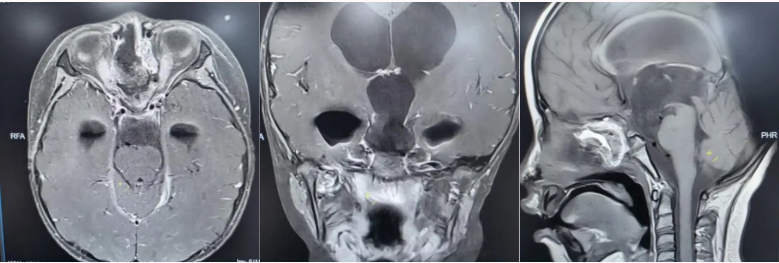

术后垂体MRI增强检查

手术中,团队借助高清4K神经内镜,凭借精湛的显微操作技术,细致分离肿瘤与周围神经、血管的粘连。历经3小时,肿瘤被完整切除,下丘脑、垂体柄、视神经等重要结构均得到完好保护。术后病理确诊为颅咽管瘤。

在医护团队的精心照护下,欢欢神经功能障碍明显改善,视力逐渐恢复,头痛症状完全消失,梗阻性脑积水得到有效缓解。之后顺利拔除脑室引流管,未出现脑脊液漏、感染等并发症,内分泌功能也通过药物获得精准调控。